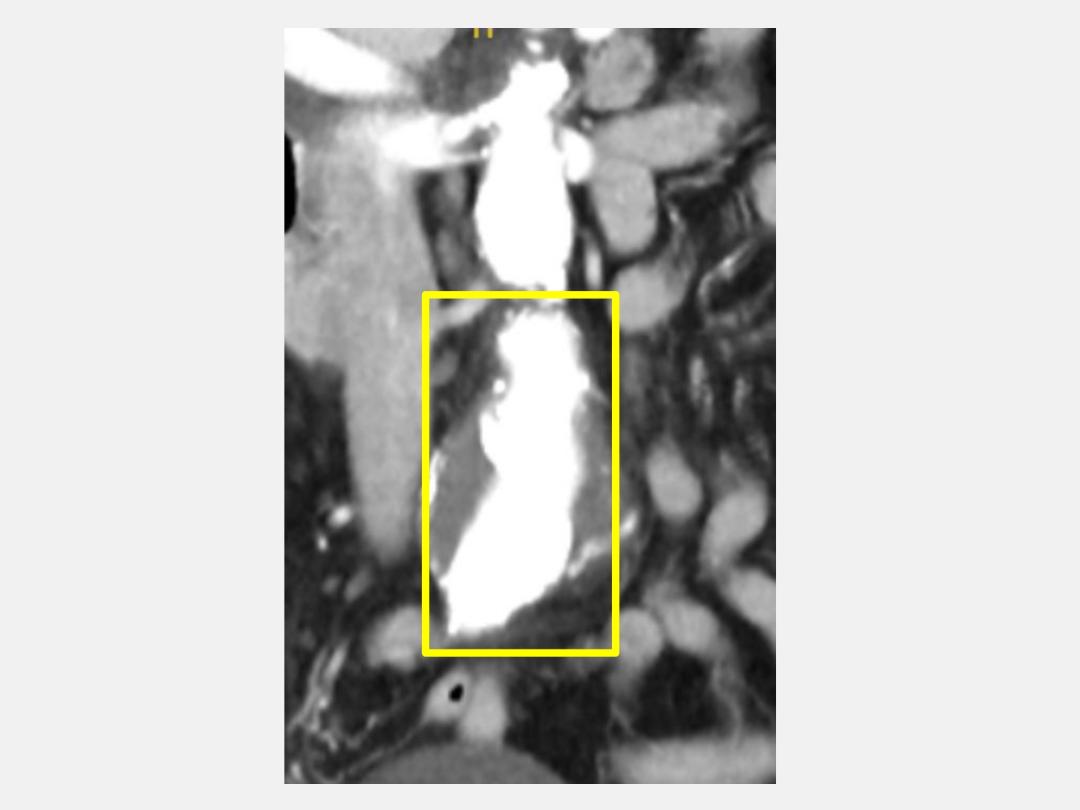

97歲陳奶奶的血壓控制不規律,且罹患腹部主動脈瘤,平常在仁愛長庚合作聯盟醫院(大里仁愛醫院)心臟血管外科門診持續追蹤。某日因劇烈腹痛被送到該院急診,測量血壓一度飆升至230mmHg,經電腦斷層精密檢查發現,其腹部主動脈瘤直徑已從原先4公分於短期內急劇擴大至5.5公分以上,瀕臨破裂邊緣,由於其血管壁極薄,這顆「隱形炸彈」隨時可能爆發導致嚴重腹腔大出血,引發致命危機。心臟血管外科團隊面對高齡手術的高風險壓力,採用局部麻醉搭配微創主動脈支架置放術(EVAR),在短短40分鐘內完成手術。陳奶奶術後並未出現呼吸道併發症,術後兩天即出院,回到家還能維持日常習慣爬樓梯拜拜,令家屬直呼:「微創技術真的是高齡者的福音!」

心臟血管外科顏旭霆醫師說,腹部主動脈瘤是指腹部的主動脈因為血管壁變弱而擴張變形,形成「瘤樣膨脹」。當腹部主動脈瘤直徑持續變大,會有破裂風險,可能造成嚴重內出血而危及生命,高齡(常見於65歲以上)、高血壓、抽菸、家族史,以及動脈粥狀硬化者是高危險族群。大多數腹部主動脈瘤無明顯症狀,常因健檢或影像檢查時意外發現,若出現腹部搏動感、持續性腹痛或背痛、昏厥或休克(可能是破裂徵兆)的症狀,需儘速就醫。治療方式除了觀察追蹤(直徑小於5公分,無症狀者),可用外科手術修補和微創血管內支架置放術。